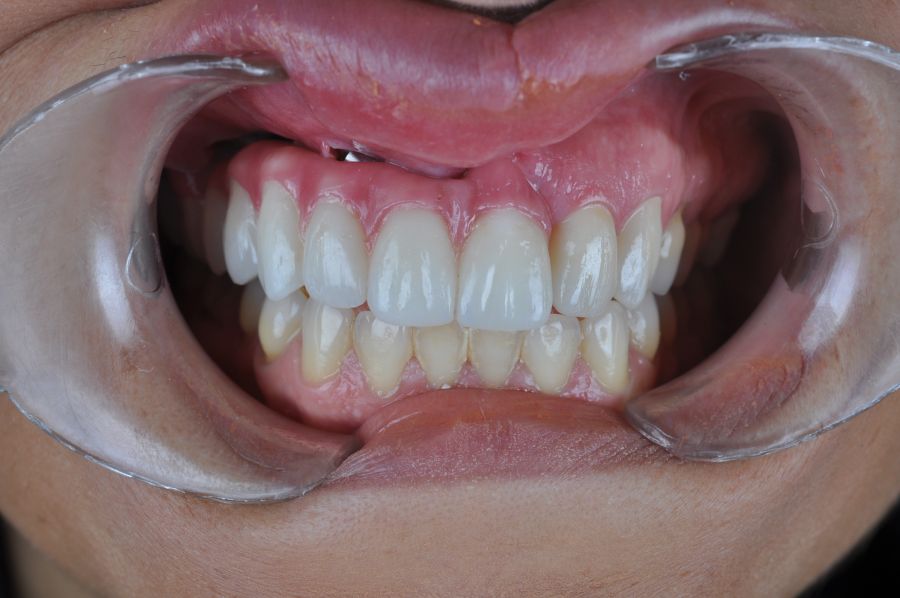

El día de la colocación de las estructuras, se arenó el interior de las coronas dentosoportadas con óxido de aluminio de 50 m y fueron cementadas con cemento de resina Multilink Ò. El puente implantosoportado se atornilló al torque indicado (20Nw) (Figuras 14, 15, 16 y 17).

En el seguimiento a 4 años tras la colocación de la prótesis definitiva, no se observaron complicaciones mecánicas ni biológicas. La paciente continúa libre de enfermedad y con una correcta adaptación al tratamiento rehabilitador implantosoportado (Figura 18).